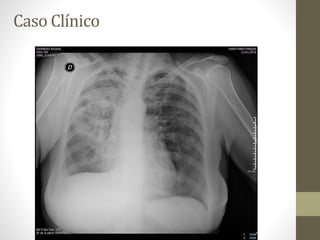

• Exámenes complementarios

 Radiografía de tórax